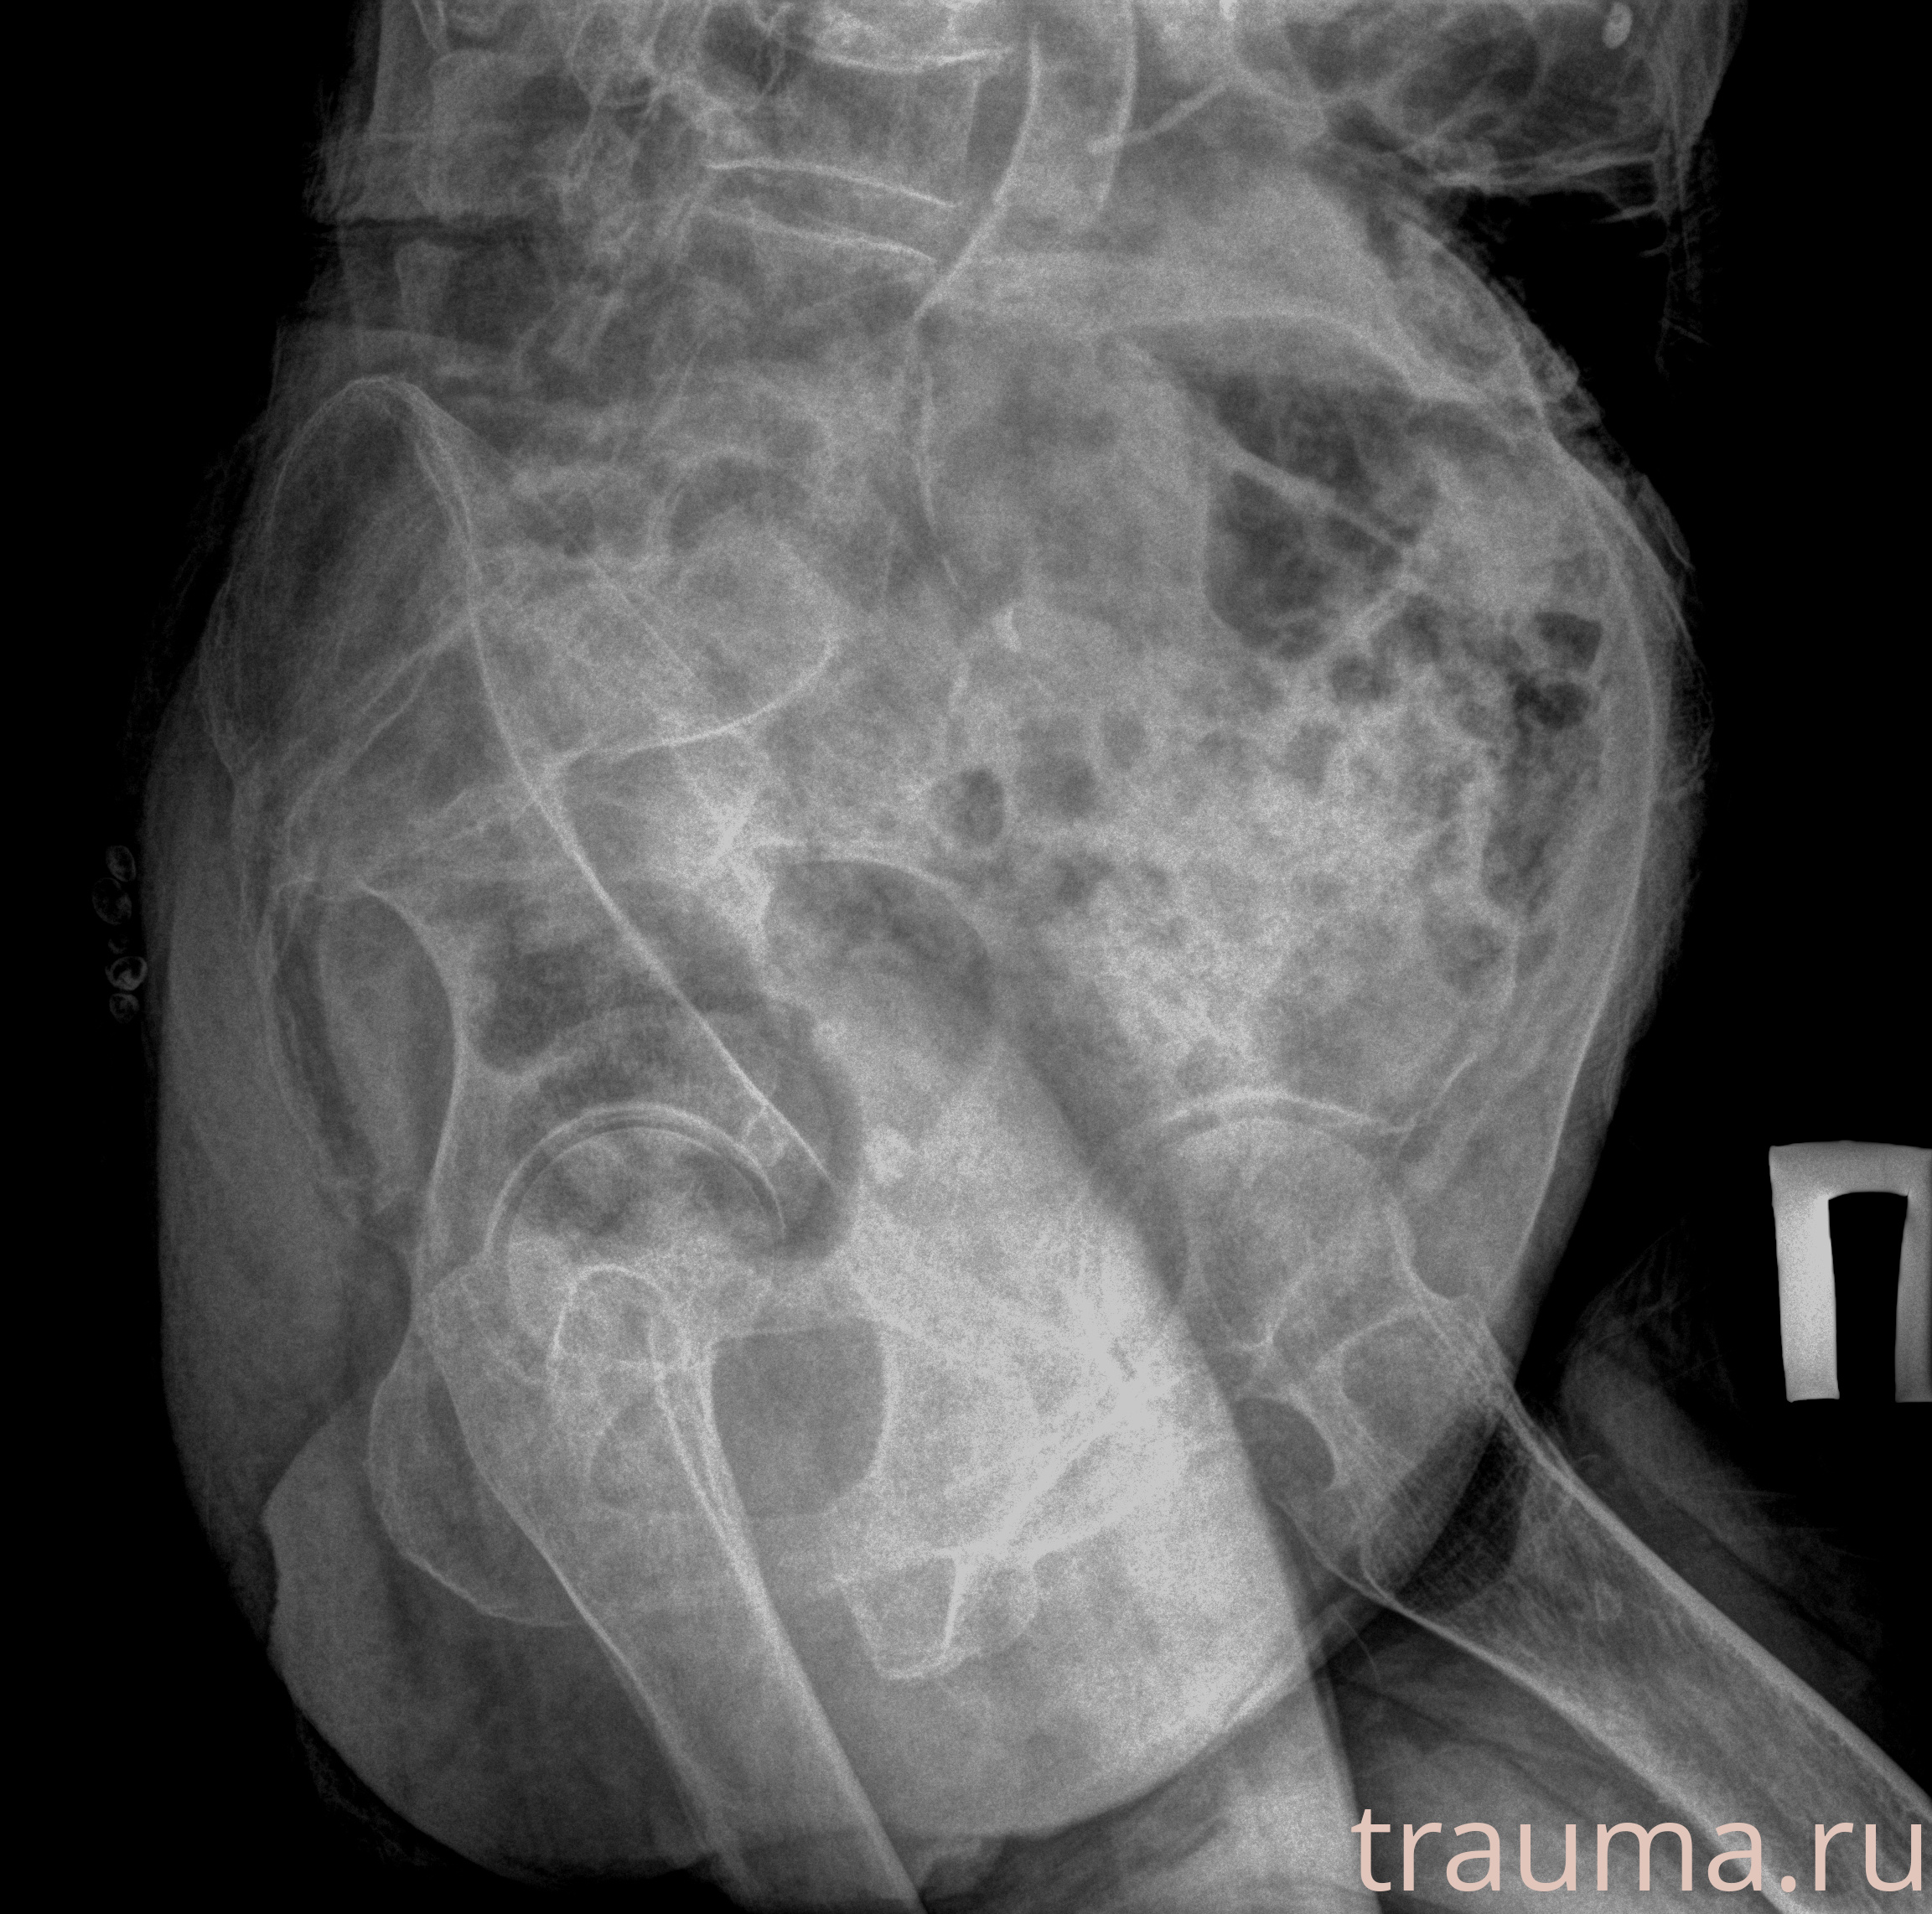

Рентгенограммы

Рентген на дому: по вашему адресу приезжает врач-рентгенолог, травматолог-ортопед с мобильным рентгеновским аппаратом, проводит диагностику травмы или заболевания, делает необходимые рентгенограммы, дает рекомендации по дальнейшему лечению. Получить качественные снимки в домашних условиях возможно благодаря уникальной методике, разработанной МосРентген Центром для института  Склифосовского